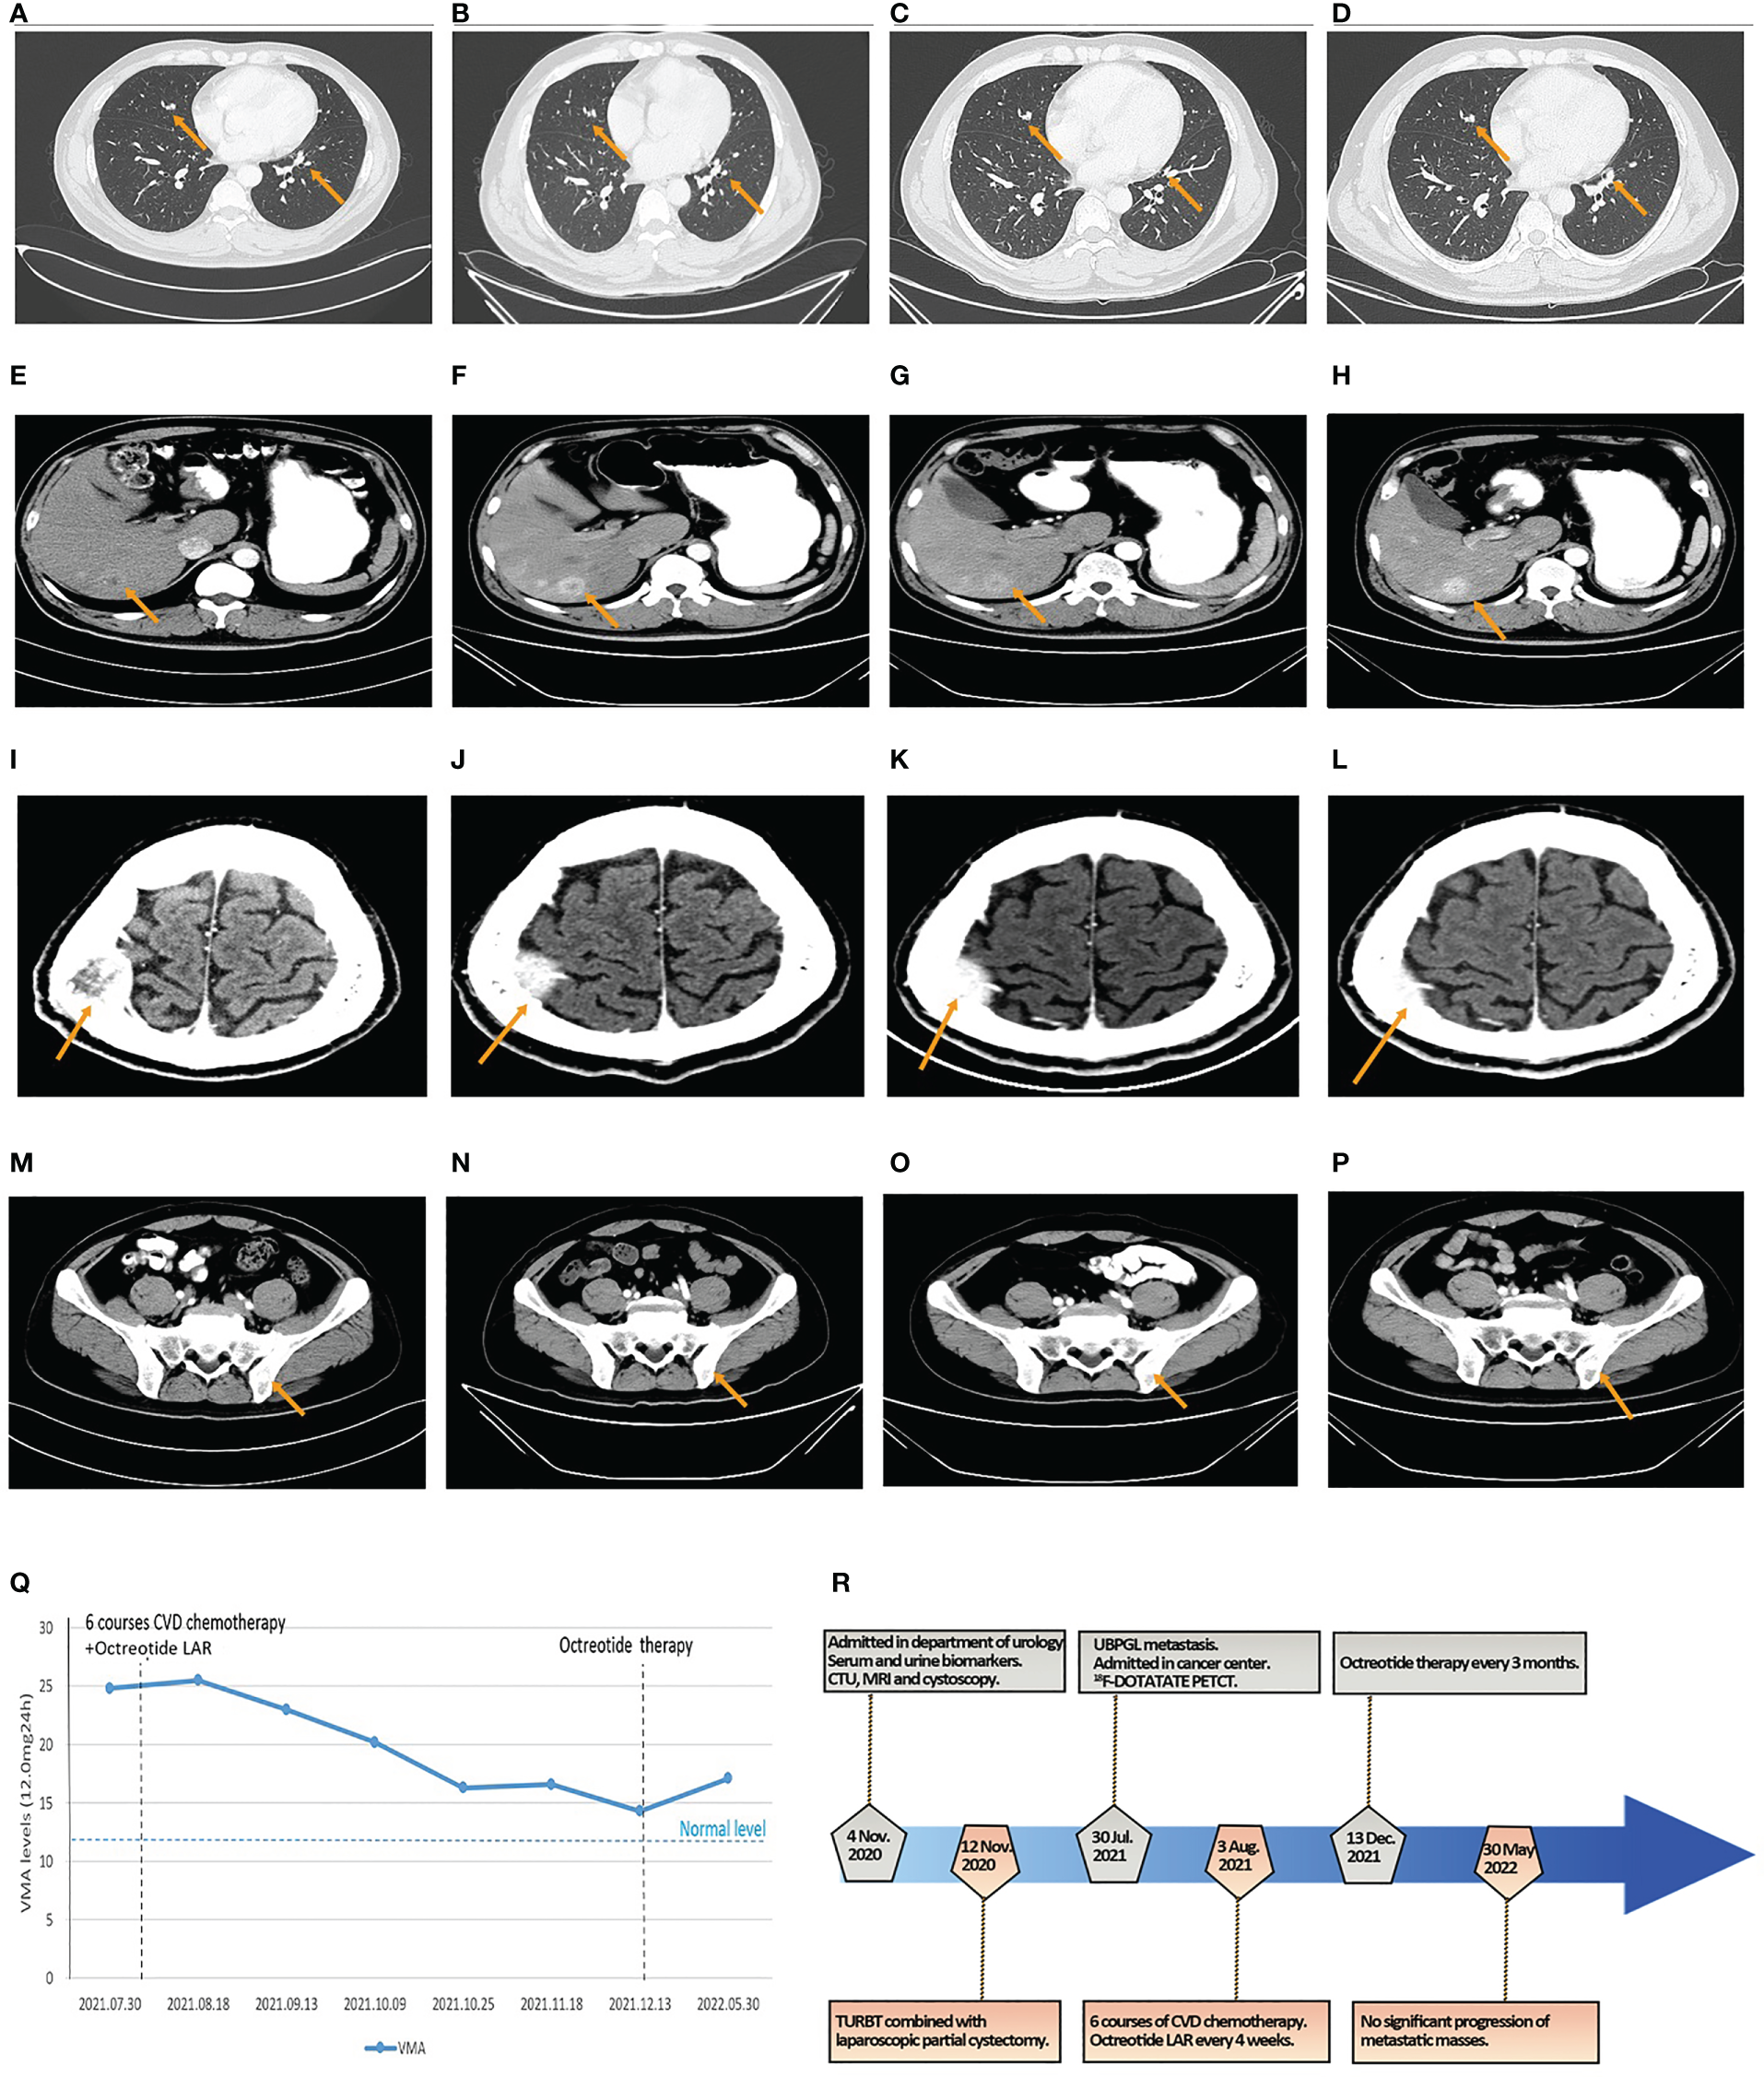

Figure 4

The results of CT and VMA in 24-h urine during octreotide plus six courses of CVD chemotherapy and the flowchart of the timeline for diagnosis and treatment process. (A–D) The size of metastatic localizations of lung had no significant progression on two courses (A), four courses (B), and six courses of chemotherapy (C), and 6-month follow-up (D). (E–H) The size of metastatic localizations of liver had no significant progression on two courses (E), four courses (F), and six courses of chemotherapy (G), and 6-month follow-up (H). (I–L) The size of metastatic localizations of skull had no significant progression on two courses (I), four courses (J), and six courses of chemotherapy (K), and 6-month follow-up (L). (M–P) The size of metastatic localizations of illum had no significant progression on two courses (M), four courses (N), and six courses of chemotherapy (O), and 6-month follow-up (P). (Q) The line graph of VMA levels in 24-h urine changes in the perioperative and chemotherapeutic period. (R) The diagnosis and treatment flowchart.

The patient received six courses of CVD chemotherapy with cyclophosphamide (1.4 g day 1), vincristine (2 mg day 1), and dacarbazine (0.4 g days 1–5) on 3 August 2021, every 16–26 days (mean 22 days). Considering the positive expression of SSTR2 in PGL tissues and the high uptake of octreotide on 18F-DOTATATE PET/CT in multiple metastases, the patient was simultaneously subjected to octreotide LAR (30 mg intramuscularly every 4 weeks) based on the recommendation of NCCN guidelines and the PROMID studies (5, 9, 10). The results of CT scans showed no significant progression in the size of the lung, liver, skull, and ilium metastases (Figures 4A–L). The levels of VMA in 24-h urine slowly declined during this period (Figure 4Q). Therefore, octreotide LAR plus CVD chemotherapy could achieve stable disease of multiple metastatic bladder PGL.

After finishing the sixth course of CVD chemotherapy and the latest treatment of octreotide LAR on 13 December 2021, the patient continued octreotide therapy (30 mg intramuscularly every 3 months) until now to control hormonally functional PGL. CT scans showed no significant progression of metastatic masses in the lung, liver, skull, and ilium (Figures 4M–P), and the level of VMA in 24-h urine was 17.10 mg/24 h after 6 months (Figure 4Q). The patient maintained a state of stable disease during the period of 6-month follow-up. The flowchart of timeline for diagnosis and the treatment process is shown in Figure 4R.